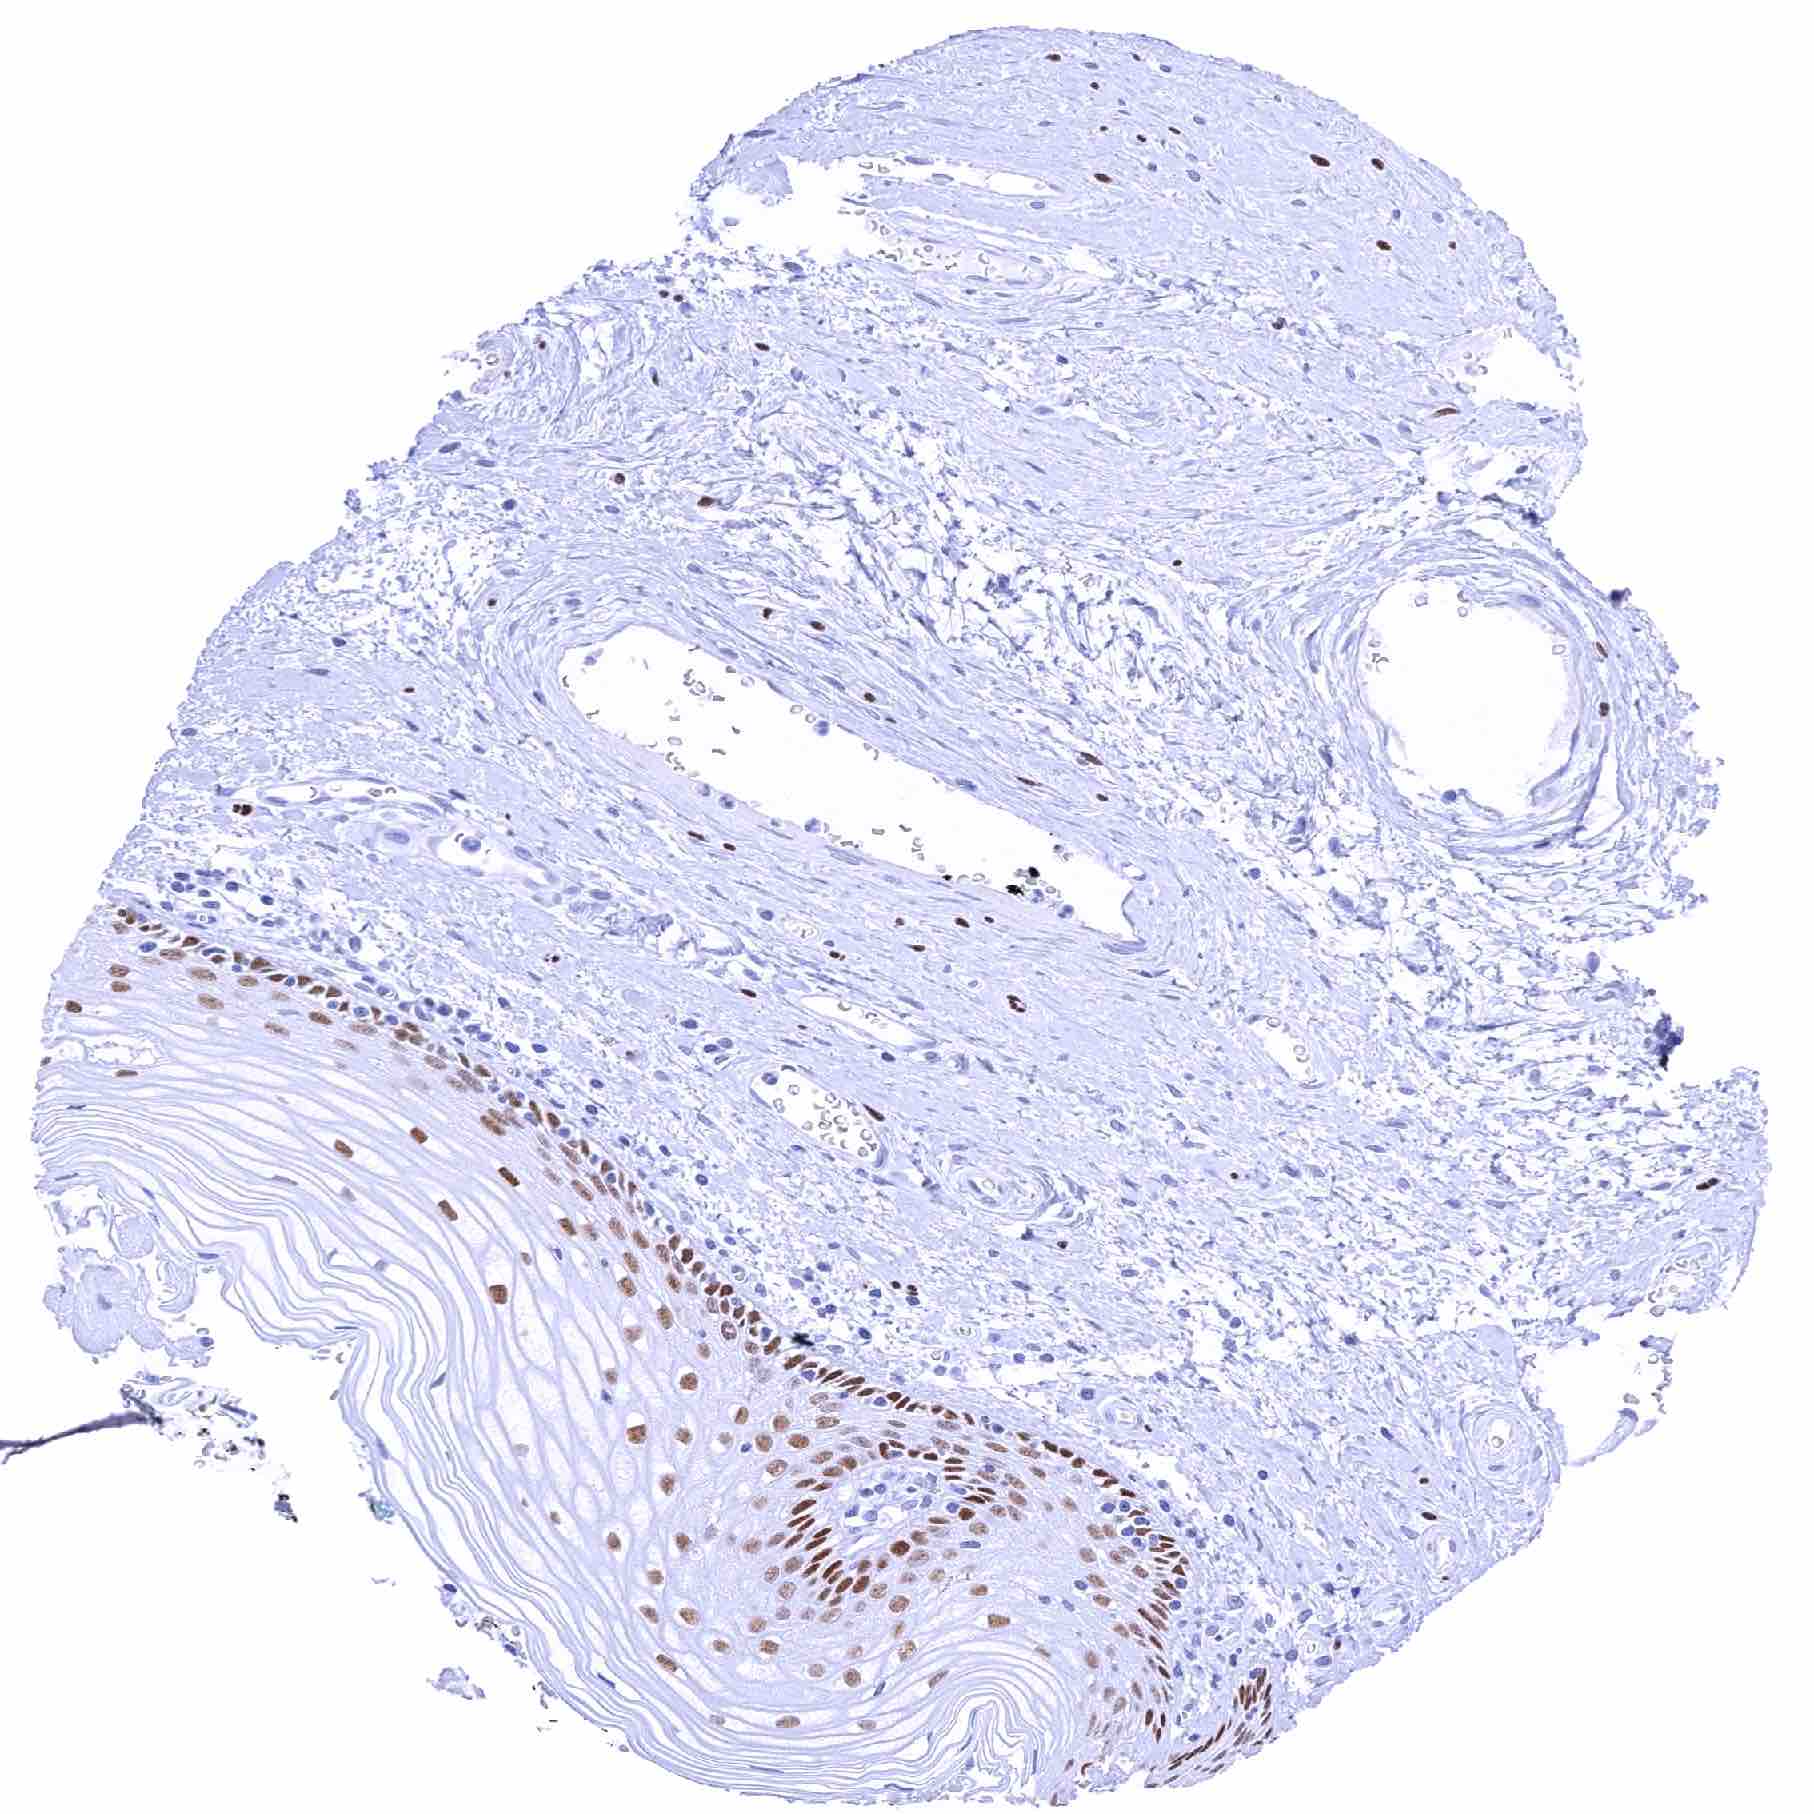

Skin – Strong SOX2 positivity few epidermis-adjacent spindle shaped (neural_) cells in the dermis

Skin, hairfollicel and sebaceous glands – Strong SOX2 positivity few hair follicle-adjacent spindle shaped (neural_) cells in the dermis